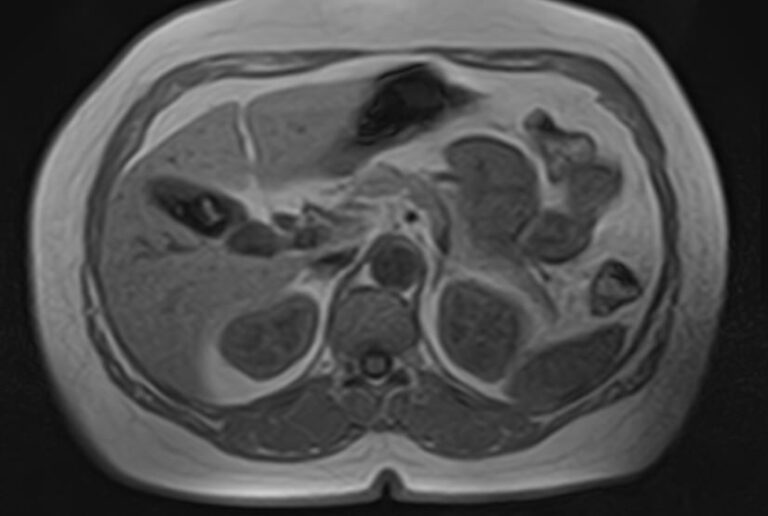

МРТ забрюшинного пространства является наиболее информативным, безопасным и доступным методом исследования, который позволяет оценить состояние органов, расположенных в данной анатомической зоне (почки, надпочечники, мочеточники), выявить возможные патологические процессы.

В клинике «Доступная медицина» установлен новейший высокопольный томограф экспертного уровня TOSHIBA VANTAGE TITAN 1,5 Тесла, на котором выполняется обследование органов забрюшинного пространства. За счет высокой индукции магнитного поля аппарат при сканировании создает изображения на плоскости превосходной четкости, затем с помощью компьютерных приложений данные преобразуются в изображения трехмерного формата, что обеспечивает точность и достоверность диагностики.

МРТ брюшного и забрюшинного пространства направлено на определение состояния нескольких органов, по результатам диагностики визуализируют:

- Аорта и нижняя полая вена. В рамках диагностики структурных патологий.

- В районе брюшной полости и забрюшинного пространства располагаются ответвления крупных сосудов.